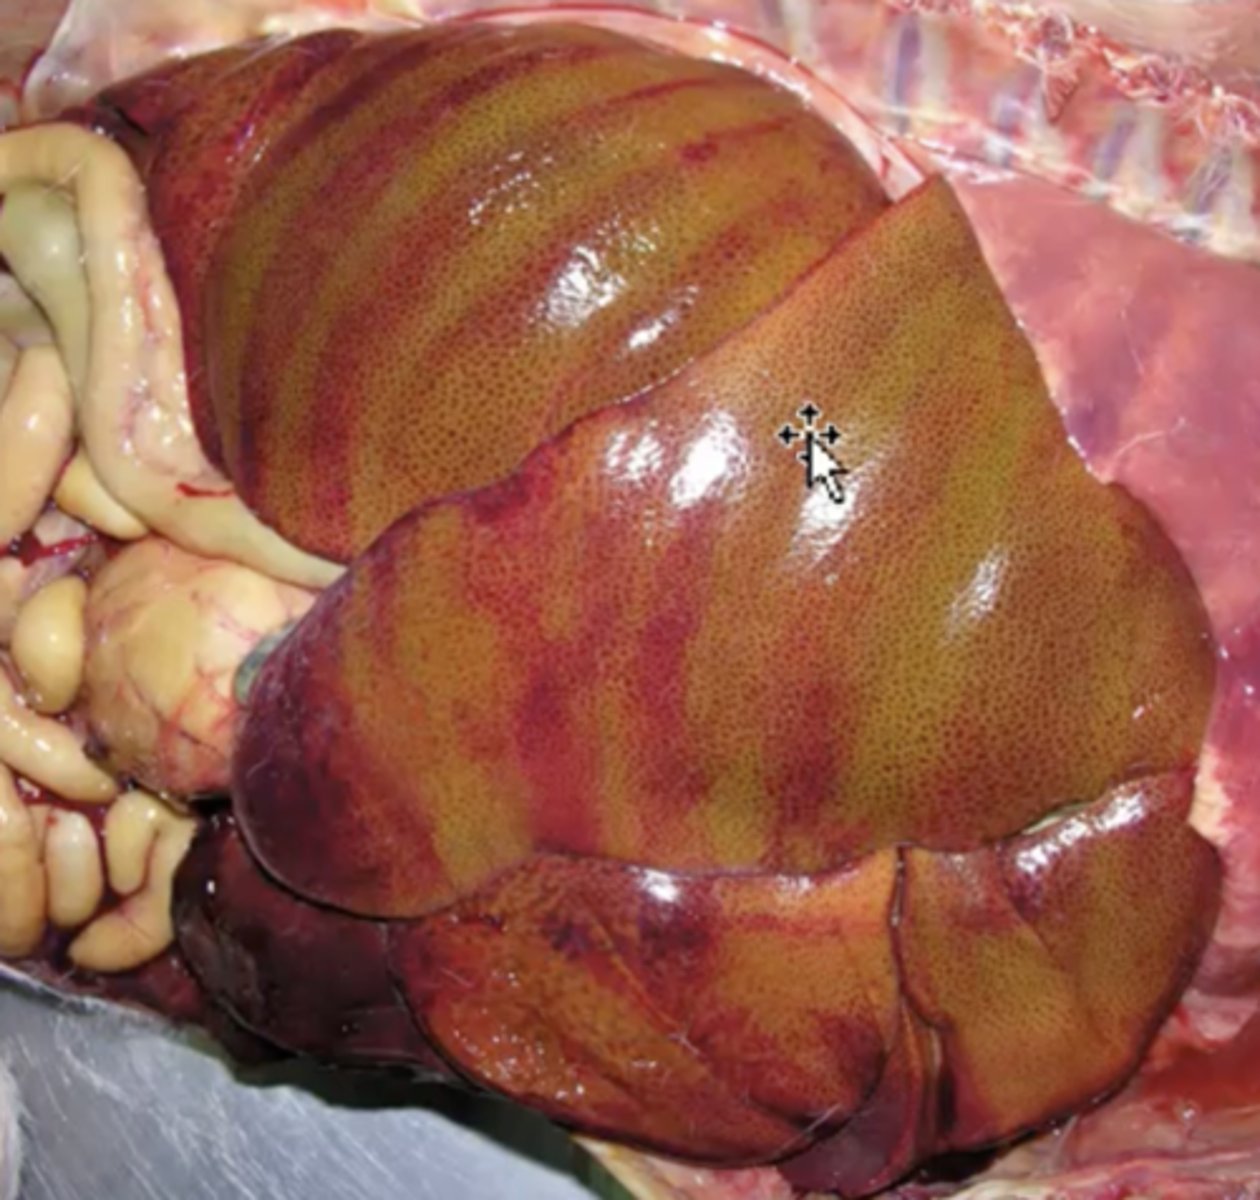

Bovine Fatty Liver Syndrome

- Caused by accumulation of lipid within the liver due to increased mobiliazation of lipids from adipose tissue = influx of fatty acids to the liver

Bovine liver: What has caused this gross appearance ?